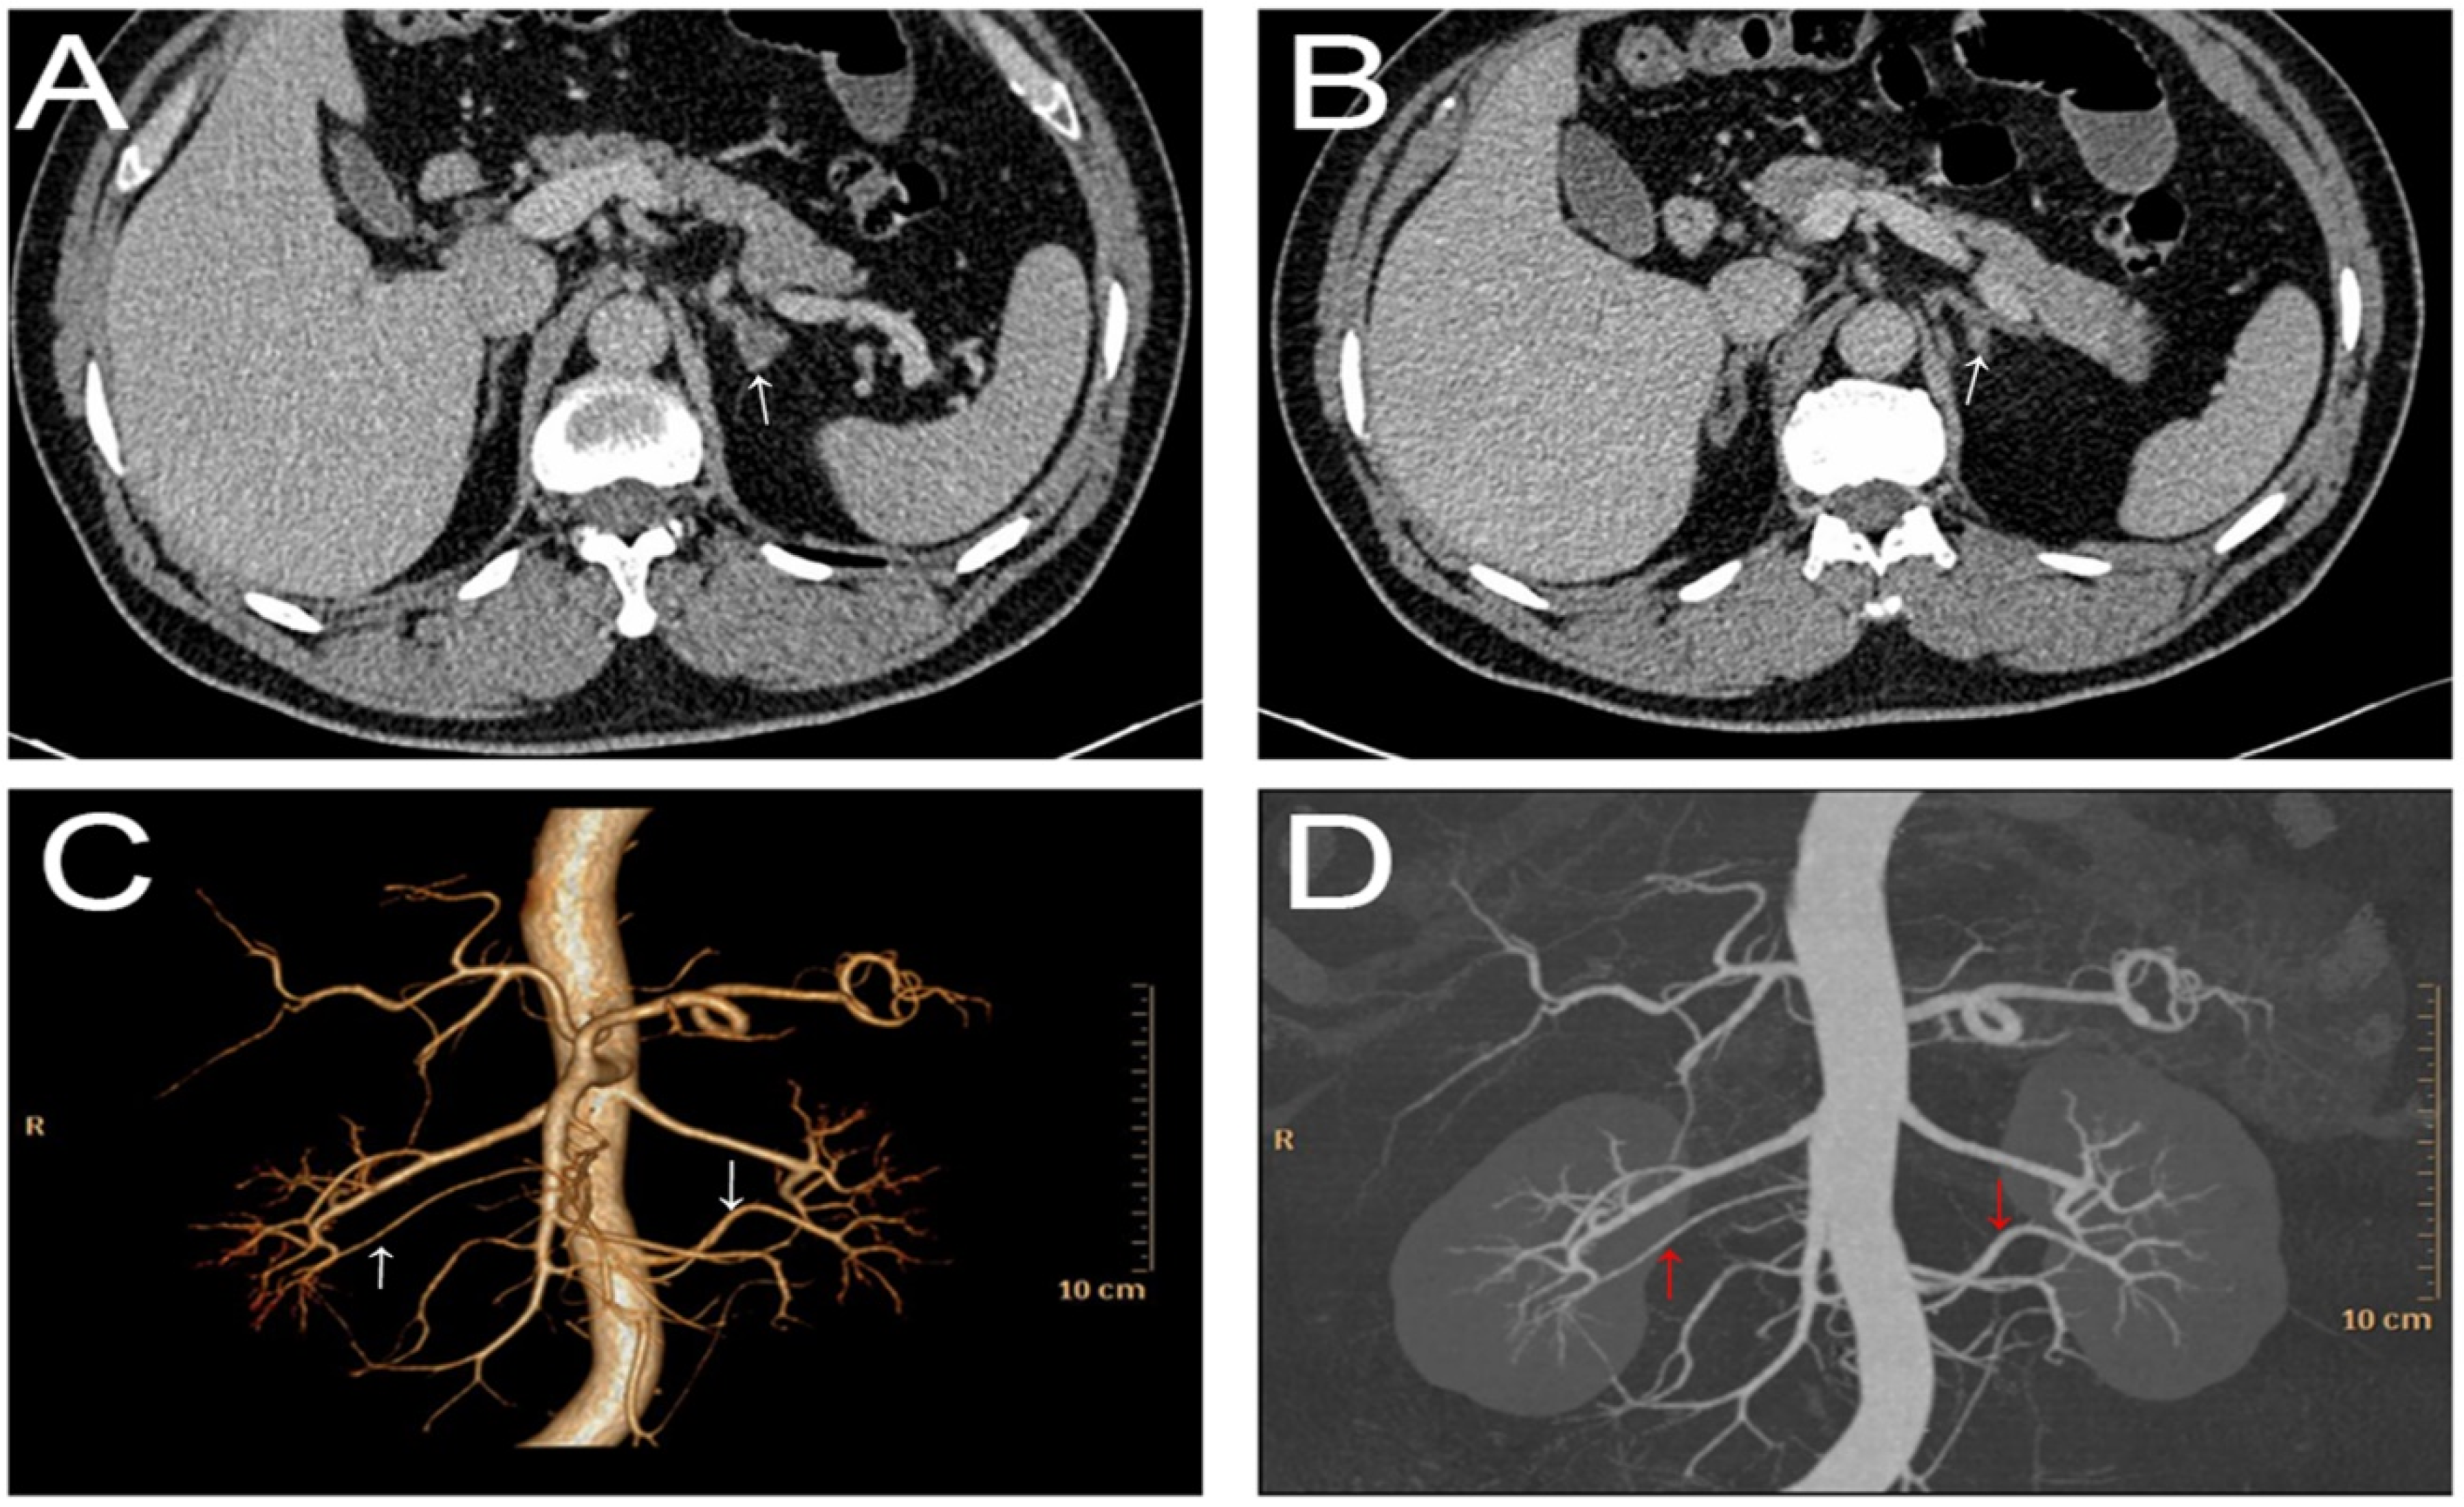

On imaging examination, ultrasound echocardiography indicated cardiac hypertrophy (interventricular septum, 15 mm; left ventricular (LV) end-diastolic diameter, 49 mm; LV posterior wall thickness, 15 mm; LV mass index, 145 g/m2; LV ejection fraction, 61%). Carotid ultrasonography demonstrated left carotid intima-media thickening. These findings suggested hypertension-mediated organ damage. Ultrasonography of the renal artery showed no abnormality, and carotid-femoral pulse wave velocity was also within the normal range. Fundoscopic examination showed no hypertensive or atherosclerotic changes in the retina. Technetium-99m diethylene triamine pentaacetic acid (Tc-99m DTPA) renal dynamic scintigraphy demonstrated symmetrical uptake bilaterally (left renal GFR = 39.1 mL/min and right renal GFR = 40.3 mL/min). Adrenal contrast-enhanced computed tomography (CT) showed that the left inner branch adrenal gland was thickened and had a round soft-tissue density mass with a diameter of 8 mm (Figure 1). In addition, renal CT angiography showed no stenosis of the renal arteries, but rather the presence of bilateral accessory renal arteries (Figure 1).

Figure 1.

Adrenal contrast-enhanced CT. (A) The white arrow showed a round soft-tissue density mass with a diameter of 8 mm; (B) The white arrow showed the left inner branch adrenal gland was thickened. CTA showed no stenosis of the bilateral renal arteries and the presence of bilateral renal accessory arteries (pointed by the white arrow in (C) and red arrow in (D)).